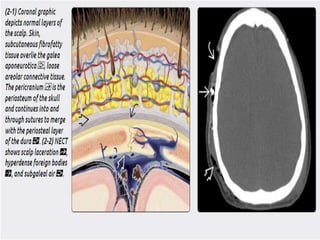

 Scalp injury –

1) laceration-Focal discontinuity, soft tissue

swelling, and subcutaneous air are commonly

identified in scalp laceration. Wood fragments

are often hypodense, whereas leaded glass,

gravel, and metallic shards are variably

hyperdense.

2) Hematoma- cephalohematoma and subgaleal

hematoma. The latter is more severe n can

cause hypovolemia and hypotension.